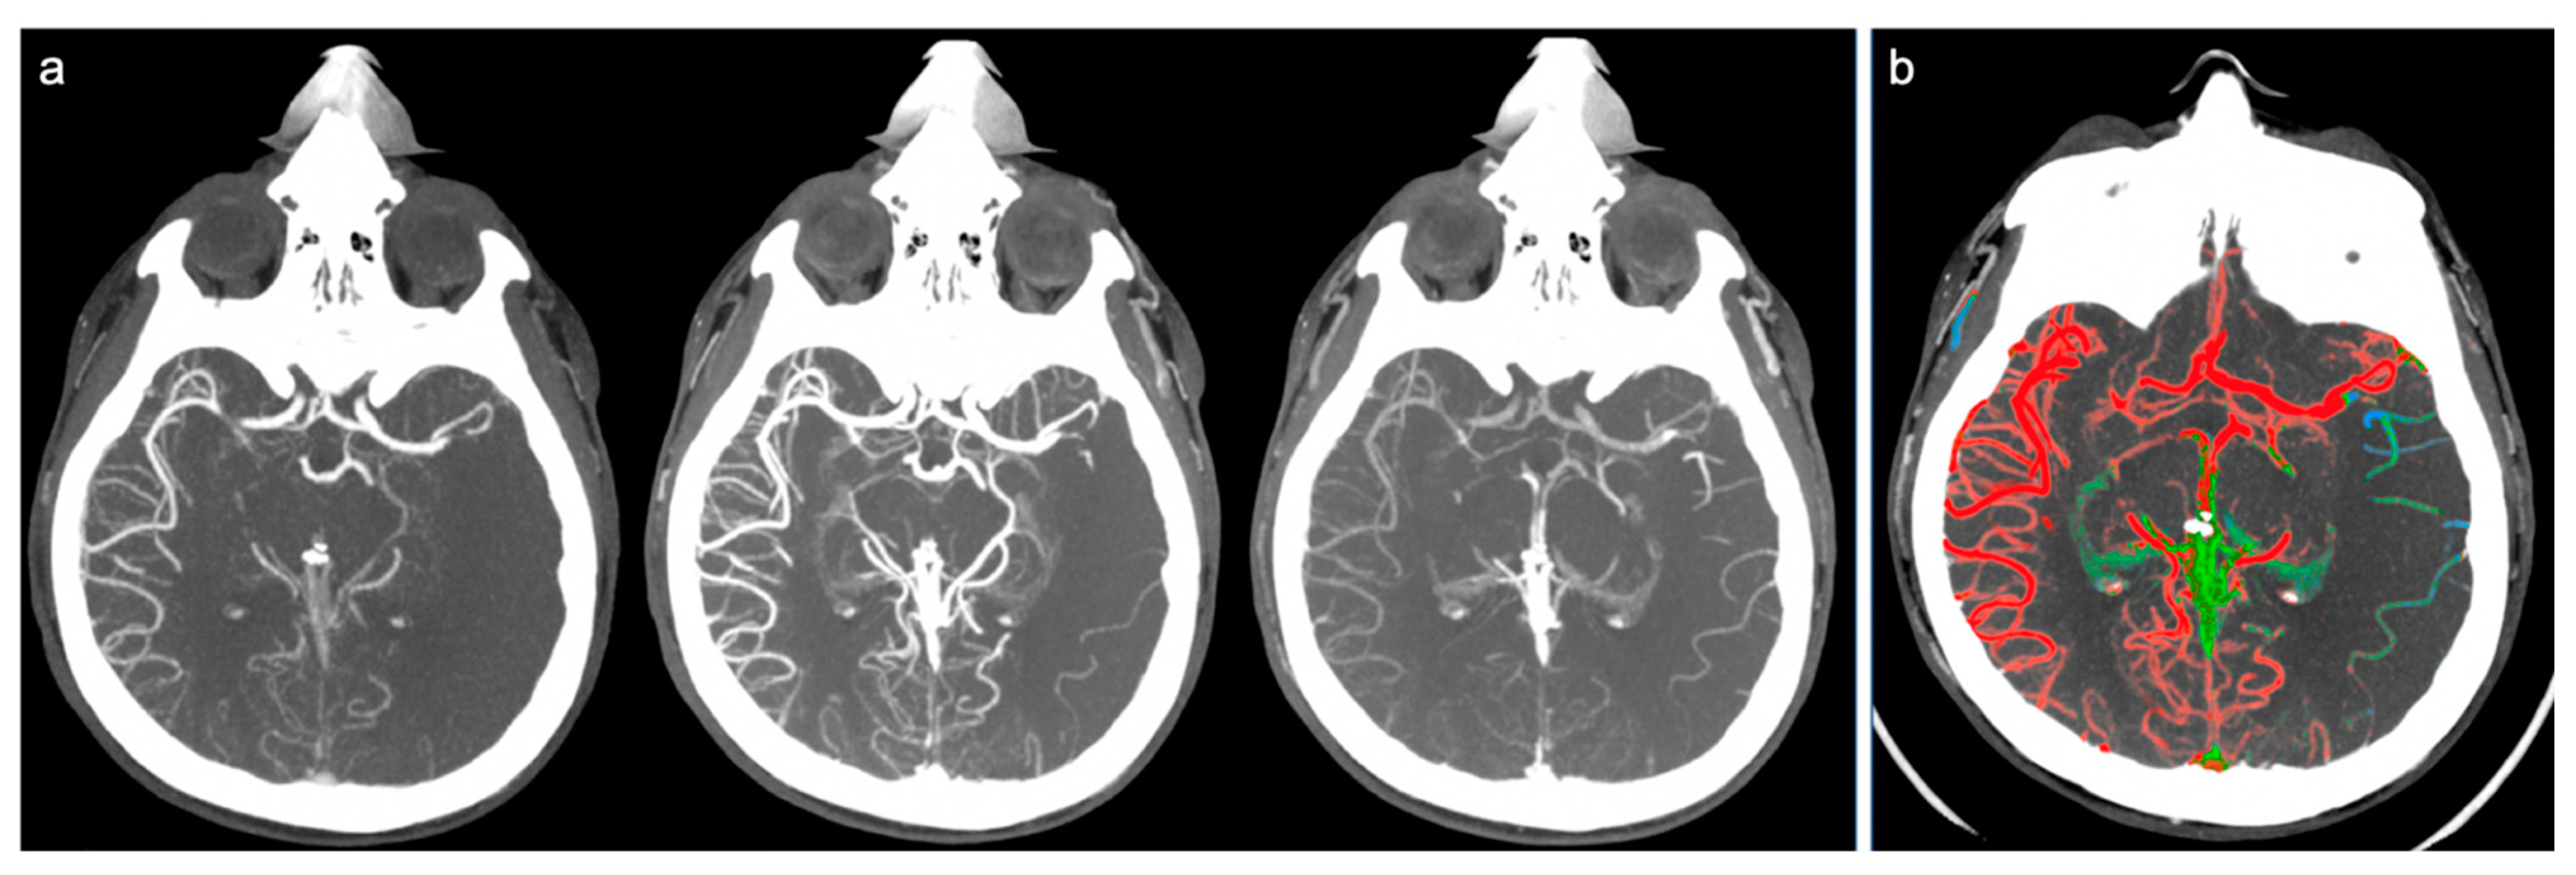

Figure 2.

Example of intermediate collateral circulation at ColorViz. (a) mCTA shows a left-sided M1 segment occlusion with intermediate pial artery filling; (b) ColorViz map shows predominant green vessels in the affected territory downstream from the occlusion (score of 2).